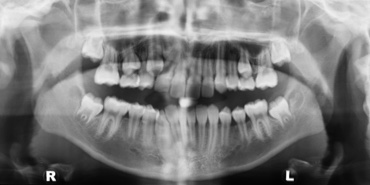

Lateral Cephalometric X-ray of the head

Orthopantomograph X-ray of the teeth and jaws